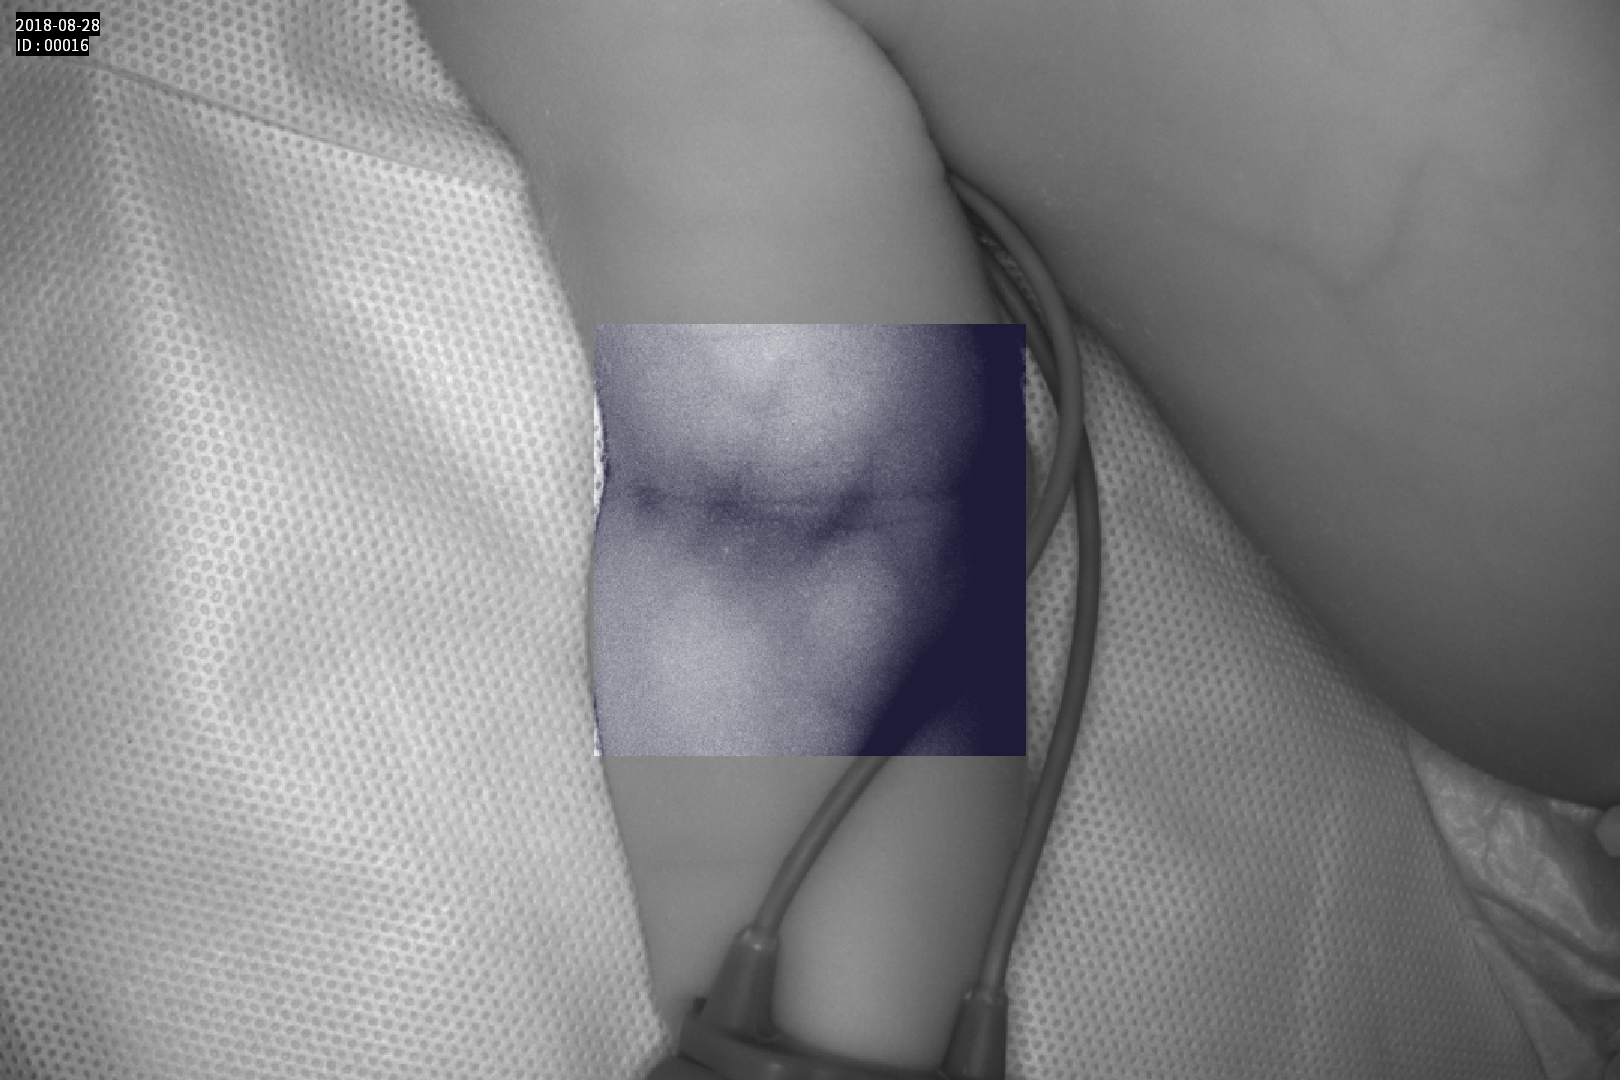

Dispozitiv medical portabil, non-contact, ce ajută la vizualizarea venelor pentru efectuarea puncției venoase, intervențiilor chirurgicale plastice, diagnosticul venelor varicoase.

Grad mare de detecție a venelor greu vizibile până la 10 mm adâncime (inclusiv vene faciale)

Imaginea venelor este proiectată pe monitorul propriu în timp real si ajută la identificarea corectă și precisă

Multiple aplicații de vizualizare vene atât la sugari cât și la pacienții obezi sau în urgențe indiferent de tonul de culoare a pielii